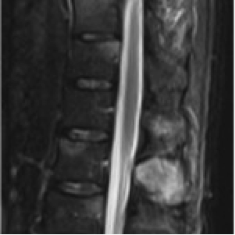

Abb. Tumor an der Wirbelsäule vor der Operation

An der Wirbelsäule werden ca. zwei Drittel aller Knochentumore diagnostiziert. Diese werden auch als Skelettmetastasen bezeichnet und lösen neben Schmerzen an der Wirbelsäule und einer Allgemeinsymptomatik, wie z. B. Leistungsabfall und Gewichtsabnahme, auch neuronale Störungen oder Lähmungen bis hin zum akuten Querschnittssyndrom aus.

Dort finden wir neben primären Tumoren der Wirbelsäule wie dem Plasmozytom auch gutartige Neubildungen wie das Hämangiom oder Knochenzysten. Zum Großteil handelt es sich allerdings um sog. sekundäre Lokalisationen eines primären Tumors, also Metastasen: z. B. von Mamma-, Prostata-, Bronchial-, Nierenzellkarzinomen oder Lymphomen. In einigen Fällen kann der Primärtumor der Metastasen nicht gefunden werden. In diesen Fällen sprechen wir von einem CUP–Syndrom (Cancer of Unknown Primary), einer Krebserkrankung mit unbekanntem Primärtumor.

Abb. Tumor an der Wirbelsäule nach der Operation

Zuerst führen wir eine ausführliche Anamnese und klinische Untersuchung durch. Zudem setzen wir bildgebende Verfahren wie die Computertomografie zur Beurteilung der Stabilität von Wirbelkörpern ein. Die Magnetresonanztomographie (MRT) setzen wir zur Beurteilung der Ausdehnung von Tumoren in den Spinalkanal sowie der lokalen Knochenzerstörung ein. Die Szintigrafie schließlich gibt uns Auskunft über etwaige sonstige Lokalisationen von Metastasen im gesamten Skelett.

Bei akuten Querschnittslähmungen steht die sofortige Operation mit Freilegung und Entlastung des Rückenmarkes sowie Stabilisierung der Wirbelsäule im Vordergrund. Bei allen anderen Formen sollte nach Diagnosefindung, d. h. Bestimmung der Art des Tumors durch eine Gewebeentnahme, über das weitere Vorgehen entschieden werden. Die genaue Art und Reihenfolge der durchzuführenden Therapieformen (Bestrahlung, Chemotherapie, Hormonbehandlung, Operation) wird häufig in Zusammenarbeit der beteiligten verschiedenen Fachrichtungen festgelegt. So ermöglichen wir eine optimale und individuelle Behandlung und erhöhen die Erfolgswahrscheinlichkeit einer Therapie.